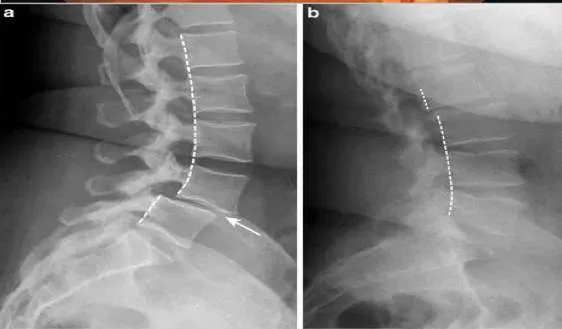

Question 18. Straight Leg Raising (SLR)

In SLR after you perform the test, to further assess the neurological tissue, move out of the painful range & then either do:

Normally 80 โ 90 degrees no pain

It will be limited by sciatica pain in lumbar disc prolapse. (<70 ) โ (exactly from 30 to 70)